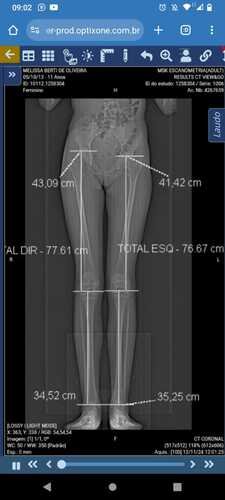

Agora, com 11 anos, enfrento uma nova batalha. Na última consulta de rotina anual, descobrimos que uma das minhas pernas parou de crescer enquanto a outra continua se desenvolvendo. Hoje, tenho uma diferença de 3 centímetros entre as minhas pernas, e a única maneira de corrigir isso é com uma cirurgia chamada epifisiodese, que precisa ser feita com urgência, antes que o crescimento continue. Ela deve acontecer ainda esse mês.

Amigos, primeiramente, quero agradecer de coração por todo o apoio e carinho que recebi até aqui! Infelizmente, houve uma mudança no planejamento da minha cirurgia. Após a tomografia, o médico descobriu que será necessário um procedimento adicional, com a colocação de parafusos na minha perna. Isso significa que precisaremos de materiais especiais e que o custo do hospital aumentará.